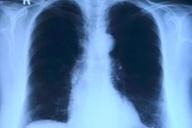

Туберкулез обошел коронавирус по случаем смертности и снова стал самым смертоносным инфекционным заболеванием в мире.

Александра Дударчик Лечение генетика Наука и Технологии 8 Февраля 2023Туберкулез является одной из самых опасных болезней, потому что способен не только поражать легкие, но и другие органы.